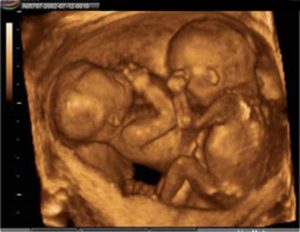

Живот будущей матери уже ощутимо поднялся над лобком, и она может испытывать трудности с дыханием. Малыши достигли длины примерно в 27 см и веса в 400 грамм.

УЗИ на этом сроке может показать разницу в весе и росте близнецов, однако это не является поводом для беспокойства.

Каждый ваш малыш на этой неделе весит почти 500 гр и имеет длину 28-29см. Из-за периода интенсивного роста вашей двойни в ближайшие недели вы можете испытывать довольно сильный дискомфорт.